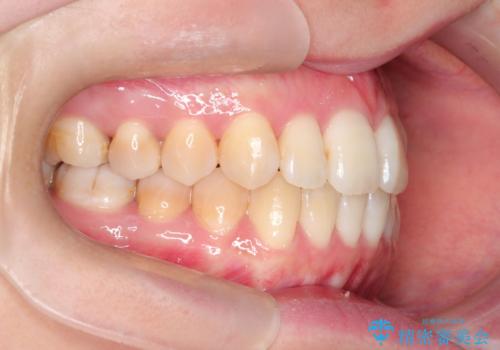

- 前歯のガタガタと、かみ合わせを改善したいとのことで来院されました。

下顎の歯が、上顎の歯に対して前方に位置していたので、下顎の歯を後方に移動させるのと、歯と歯の間を削りスペースを作り、歯を並べる計画としました。

お仕事の関係で使用時間が制限されるときもあり、治療期間が予想より少し長くなりましたが、装置をつけずに治療を終えることができました。